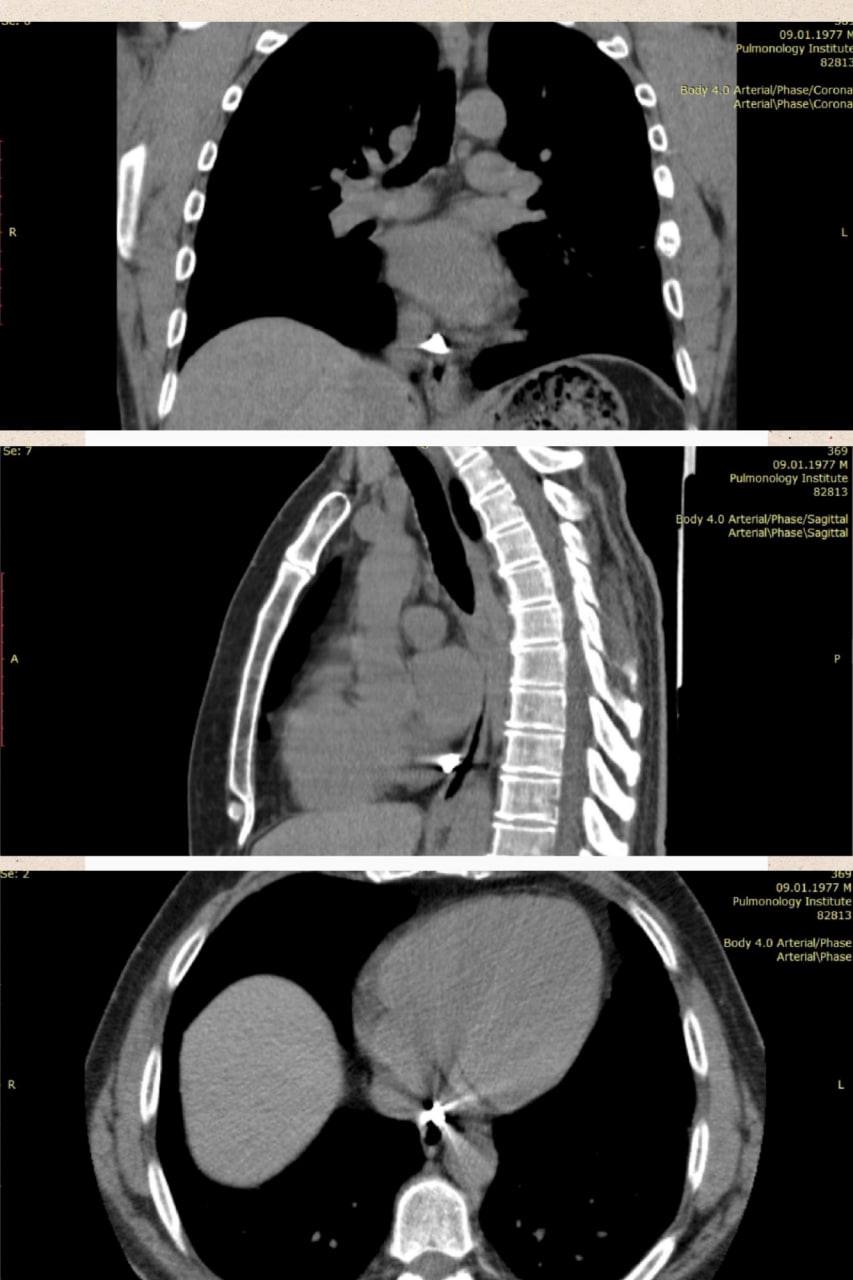

На КТ дослідженні фахівці побачили уламок значних розмірів – 8×9 мм, який застряг в перикарді (зовнішня сполучнотканинна оболонка серця – тонкий, але щільний мішок, в якому розташоване серце).

Лікарі зазначили, що дане специфічне розташування суттєво ускладнювало оперативне втручання.

Хірурги вирішили провести мініінвазивне торакоскопічне видалення металевого уламка, із застосуванням магнітного інструментарію для евакуації його з товщі тканини.